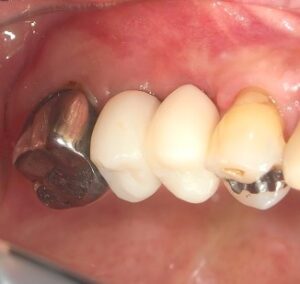

インプラントが噛んでいたくない

発音支障がない

歯肉が腫れない

相手のは(対合歯)が痛くない

仮歯の削れ具合

はぎしりがスムーズにできているか

などの審査を4週間後に受け そこで ファイナルを完成させます。